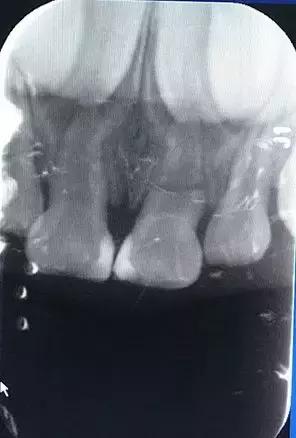

如果是没有完全脱位但是有松动和移位的乳牙,需要拍摄X片,若通过拍摄X光片,发现乳牙外伤已导致明显的根折和移位,建议择期拔除,以防根尖反复感染影响恒牙胚。